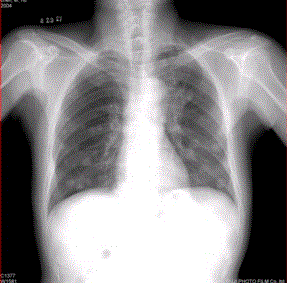

问题 患者男,45岁,因肝硬化、肝癌行肝移植术后6个月,咳嗽2周,来院复查。CR及CT影像如下图。 对于转移瘤和原发癌的关系,描述正确的有

选项 A.肺内转移最多的原发瘤为肝癌 B.原发支气管肺癌可转移到同侧和对侧 C.乳腺癌肺转移可通过血行和淋巴途径,还可经胸膜播散 D.睾丸精原细胞瘤的肺和淋巴结转移灶密度较低 E.中枢神经系统肿瘤易发生肺内转移 F.脑转移瘤中最常见的原发肿瘤为肺癌

答案 BCDE